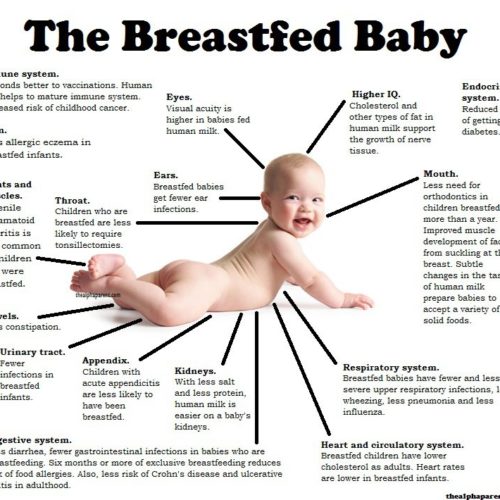

Τα παρακάτω κείμενα είναι γραμμένα από την παιδίατρο κ/α Μαλλιαρού στην ιστοσελίδα της www.mothereducation.gr Στα μαιευτήρια του ελλαδικού χώρου: • Χορηγούνται υποκατάστατα μητρικού γάλακτος λάθρα στο νεογέννητο, χωρίς καν να ενημερωθούν οι γονείς. • Υπάρχει παρακαταθήκη υποκαταστάτων μητρικού γάλακτος. • Παρέχουν υποκατάστατα μητρικού γάλακτος στο νεογνό, χωρίς την απαιτούμενη από το Υπουργείο…